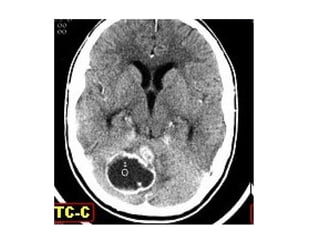

Craniofaringioma(imagem)

• Rx de crânio

– 50%

– 54 a 96% - calcificações suprasselares

• TC

– Calcificações, caráter cístico da lesão e

hiperatenuação após injeção de contraste

– Hipodensa

• RM

– Estabelece os limites e as relações da

lesão(hipotálamo, quiasma e III ventrículo)

– Limites da zona de gliose peritumoral e córtex

– Hiperintensa em T2 e intensidade variável em T1

Azul – dilatação ventricular

Amarela – cisto

Vermelho - sólida